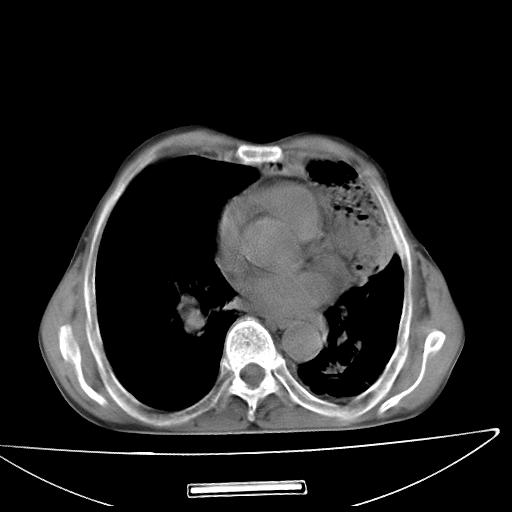

男  70岁,发烧咳嗽4天。盗汗,消瘦。无痰中带血丝,以前有肺tb病史,ct见,双肺tb,左侧胸廓塌陷,左胸膜肥厚粘连。纵隔移位,右侧胸腔积液,大家说说那个心影前左肺舌叶除了肺大炮还有炎症还是干酪性肺炎?有占位吗?我看纵隔淋巴结也大。

是胃,纵膈未见明显肿大淋巴结。

1)两肺继发性肺结核并左肺上叶肺不张,支气管扩张。2)双侧胸膜炎(胸膜增厚+少量胸腔积液)。

双肺继发性肺结核伴部分左肺毁损。